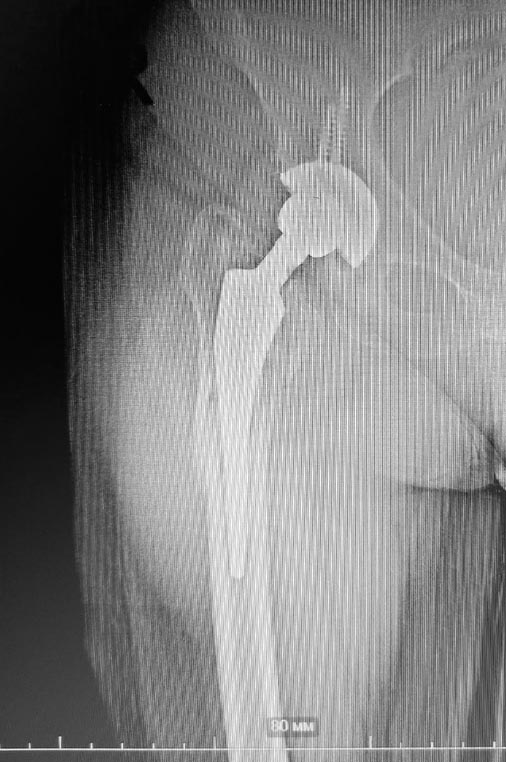

Перипротезный перелом

Пациентка М. 1966г.р. , 10.10.21 через 1 час после падения с высоты роста поступила в отделение травматологии с диагнозом : Перипротезный перелом проксимального отдела правой бедренной кости.ТЭП правого т\бедр. сустава от 2014г.

На данный момент находится на скелетном вытяжении.Дайте пожалуйста совет по дальнейшей тактике ведения пациента. Фото прилагается.

Ваш снимок только в одной проекции. Насколько можно судить это Ванкувер 2, по одноимённой классификации, ножка протеза нестабильна. Я бы рекомендовал ревизию с заменой рожки протеза на более длинную с диафизарной фиксацией, например Ревитан от Циммер/Биомет, и церкляжами.